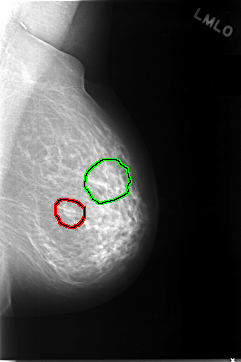

C_0038_1.LEFT_CC

FILE: C_0038_1.LEFT_CC.OVERLAY

TOTAL_ABNORMALITIES 2

ABNORMALITY 1

LESION_TYPE MASS SHAPE OVAL MARGINS ILL_DEFINED

ASSESSMENT 4

SUBTLETY 3

PATHOLOGY BENIGN

TOTAL_OUTLINES 1

BOUNDARY

ABNORMALITY 2

LESION_TYPE CALCIFICATION TYPE FINE_LINEAR_BRANCHING DISTRIBUTION CLUSTERED

ASSESSMENT 5

SUBTLETY 4

PATHOLOGY MALIGNANT